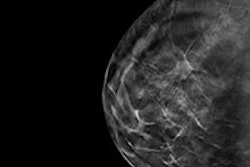

In the women's imaging section of its booth, Siemens is talking up Mammomat Inspiration Prime, the company's flagship full-field digital mammography system. Key features on Prime include an algorithm for progressive image reconstruction that replaces the scatter grid found on conventional mammography systems, lowering radiation dose by up to 30% compared with the previous Siemens model.

For better patient comfort, an Opcomp function applies compression only as long as the patient's breast is soft and pliable, stopping at the point of optimal compression, while the company's MoonLight LED panel allows breast imaging facilities to create a more relaxing environment for patients.